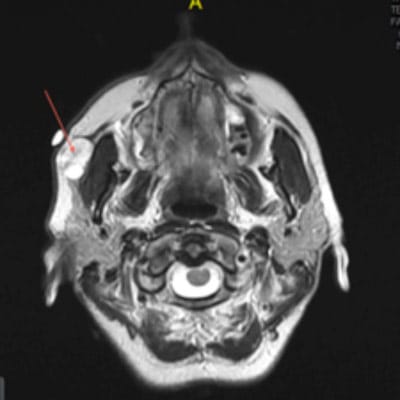

Une lithiase salivaire est une masse minérale formée de calcium que l’on appelle aussi calcul (caillou) dans le canal excréteur d’une des glandes salivaires. Il peut s’agir des glandes :

Les lithiases peuvent toucher toutes les glandes salivaires, cependant c’est la glande submandibulaire qui est le plus fréquemment atteinte.